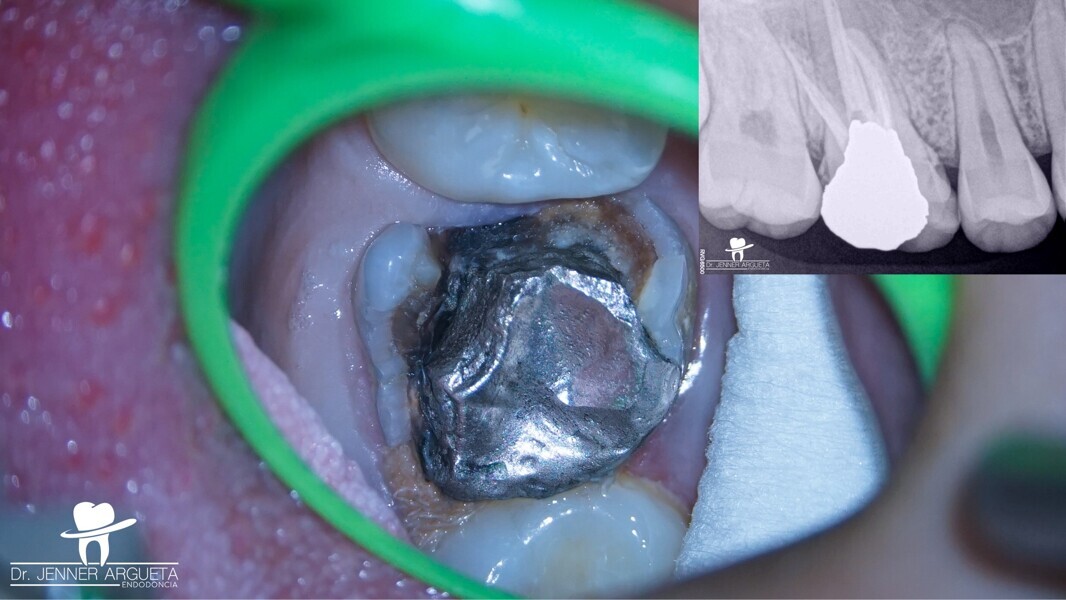

Autogenous transplantation followed by conservative root canal therapy: Three years follow-up